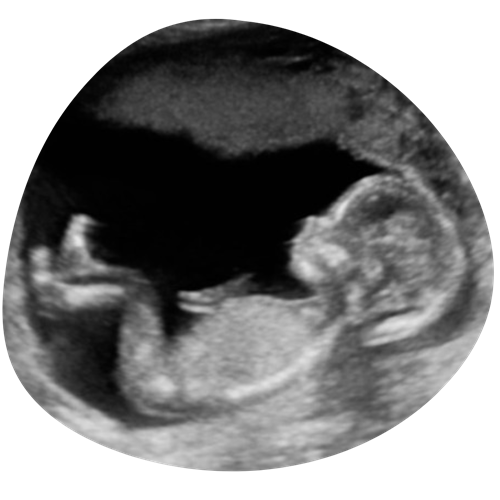

2D echo

Tijdens je hele zwangerschap kunnen we je kindje in 2D laten zien. We kunnen met 2D goed naar de structuren in het lichaampje van je kindje kijken en naar bijvoorbeeld het profieltje, handjes, voetjes etc. Geef vooral aan wat jullie graag willen zien!

€35 (15 minuten)